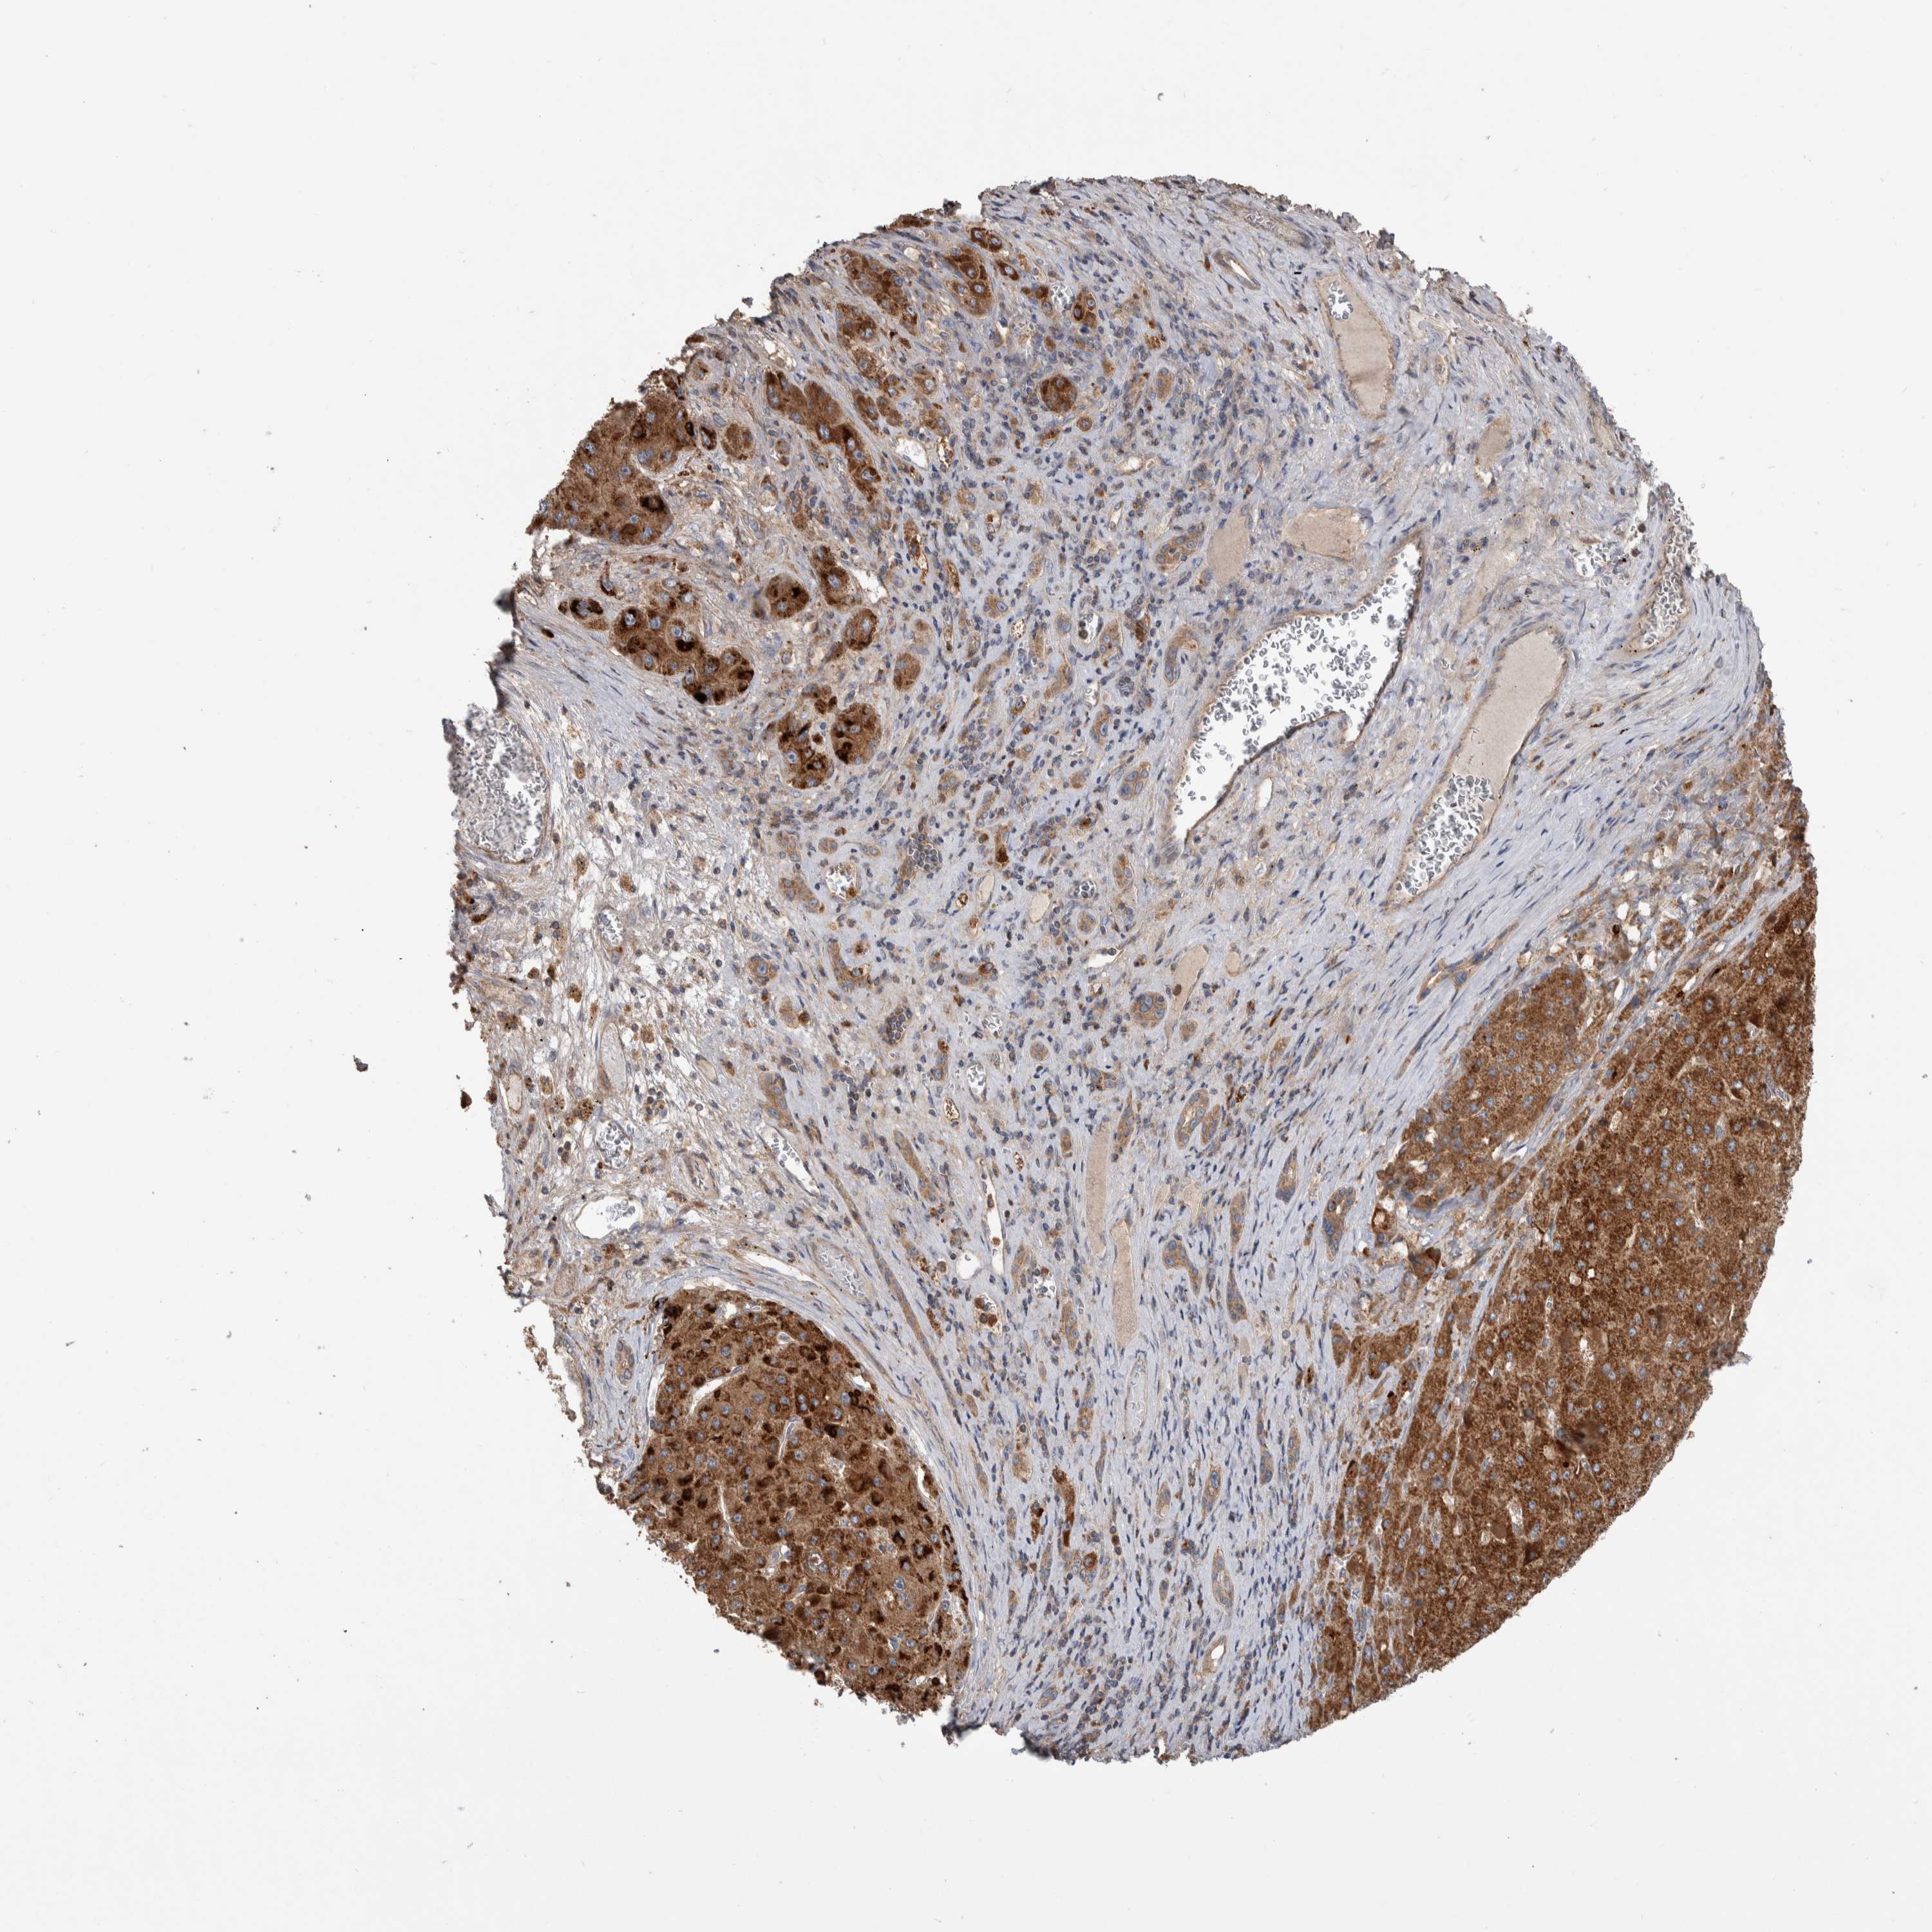

LIVER CANCER - Protein expressioni

A mouse-over function shows sample information and annotation data. Click on an image to view it in a full screen mode. Samples can be filtered based on level of antibody staining by selecting one or several of the following categories: high, medium, low and not detected. The assay and annotation is described here.

Note that samples used for immunohistochemistry by the Human Protein Atlas do not correspond to samples in the TCGA dataset.

Antibody stainingi

Antibody staining in the annotated cell types in the current human tissue is reported as not detected, low, medium, or high, based on conventional immunohistochemistry profiling in selected tissues. This score is based on the combination of the staining intensity and fraction of stained cells.

Each image is clickable and will lead to virtual microscopy that enables deeper exploration of all samples and also displays staining intensity scores, fraction scores and subcellular localization as well as patient and tissue information for each sample.

Antibody HPA023840

Antibody CAB012245

Staining

High

Medium

Low

Not detected

Intensity

Strong

Moderate

Weak

Negative

Quantity

>75%

75%-25%

<25%

None

Location

Nuclear

Cytoplasmic/membranous

Cytoplasmic/membranous,nuclear

Cholangiocarcinoma

Carcinoma, Hepatocellular, NOS